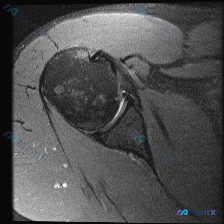

整理了一份有意思的肩关节MRI读片病例,问题一开始聚焦在「软组织积液」上,但梳理下来发现这个病例很容易踩坑,分享一下我的思路。 一、影像基本信息 这是一份肩关节冠状位T2序列MRI,我们按结构逐层看一下观察到的征象: 1. 冈上肌腱:肱骨大结节止点处可见条带状局灶异常高信号,贯穿肌腱全层,从关节面延...

整理了一份肩关节MRI的病例资料,临床申请的检查目的是排查盂唇病变,不过仔细阅片后发现核心异常好像不在盂唇那边? 先放已明确的影像基础信息: - 序列修正:初始标注为T1序列,实际影像符合质子密度压脂(PD FS)或T2压脂序列特征,对积液、肌腱损伤敏感 - 核心可见表现:肱骨大结节处肌腱信号异常、...

最近看到这份肩部MRI病例,问题问的是影像里的软组织积液怎么解释,整理了完整的读片和分析思路分享给大家。 一、影像基本信息 这是一张肩关节冠状位T2序列MRI,扫描范围覆盖肩峰、肩锁关节、冈上肌肌腱、肱骨头、肩关节间隙和三角肌,我们先明确正常信号基准:T2序列正常肌腱是低信号(黑色),关节液、水肿是...

看到一个肩关节MRI影像分析的病例材料,影像为冠状位T2加权图像,主要发现如下: 1. 冈上肌腱远端附着处全层撕裂,T2序列显示高信号液体填充 2. 肩峰下-三角肌下滑囊内有明显积液 3. 盂肱关节腔内有显著液体潴留 用户的核心问题是关于「盂唇病变」的可能性。这个病例有几个点值得讨论: - 冈上肌腱...